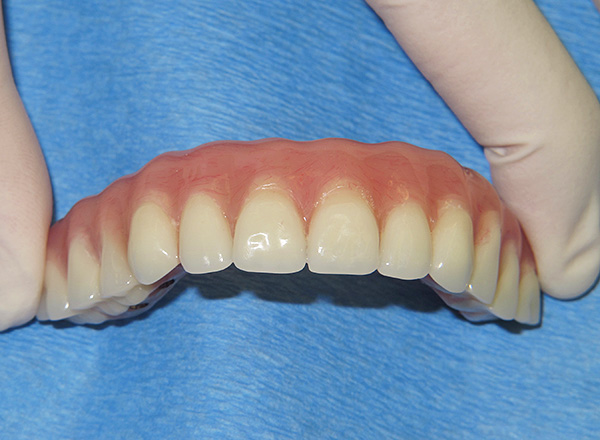

Per l'impianto con carico immediato, di norma vengono utilizzati impianti monocomponenti (ovvero, sono integrali con il moncone) e sono leggermente più lunghi rispetto ai disegni classici e hanno un filo più aggressivo. Ciò consente di fissarli in modo sicuro nel tessuto osseo denso - nello strato basale o nella piastra corticale, che sono caratterizzati da una maggiore forza (non hanno praticamente capillari, a differenza dello strato spugnoso, quindi non subiscono atrofia, cioè non si contraggono in volume e rimangono il più forti possibile) ). Pertanto, questo tipo di impianto dentale viene solitamente eseguito senza un'estensione preliminare del tessuto osseo, poiché nella maggior parte dei casi è possibile ottenere una buona fissazione degli impianti con i volumi disponibili.

La caratteristica più importante del metodo basale degli impianti dentali è la possibilità di protesi quasi istantanee. Vale a dire, letteralmente già 2-3 giorni dopo l'installazione degli impianti, le protesi fisse sono fisse. Sono realizzati in metallo-plastica e hanno una piccola base in plastica, la protesi è abbastanza leggera.La gomma artificiale, che in pratica non differisce nell'aspetto da quella naturale, consente di migliorare l'estetica della dentatura (si osserva spesso una lunga assenza di denti si verifica una subsidenza irregolare dell'osso con la gomma).

Le protesi immediate svolgono un'altra importante funzione: la protesi è uno stabilizzatore per impianti basali installati (li fissa in una certa posizione e impedisce loro di muoversi). Inoltre, la protesi fornisce un trasferimento del carico masticatorio agli impianti, che consente di accelerare il processo di osteointegrazione.